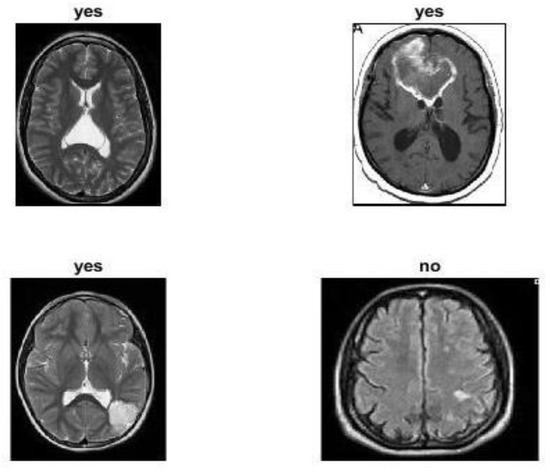

4.5. Model Evaluation Using Public Dataset